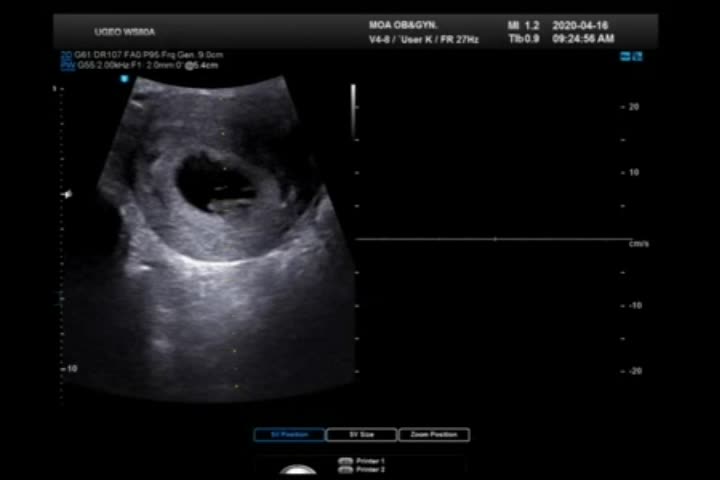

임신 6주-7주 증상 (4월 10일-4월 23일) 4월 16일은 쩨리 심장소리를 들으러 가는 날이였다..! 4월 7일 설...